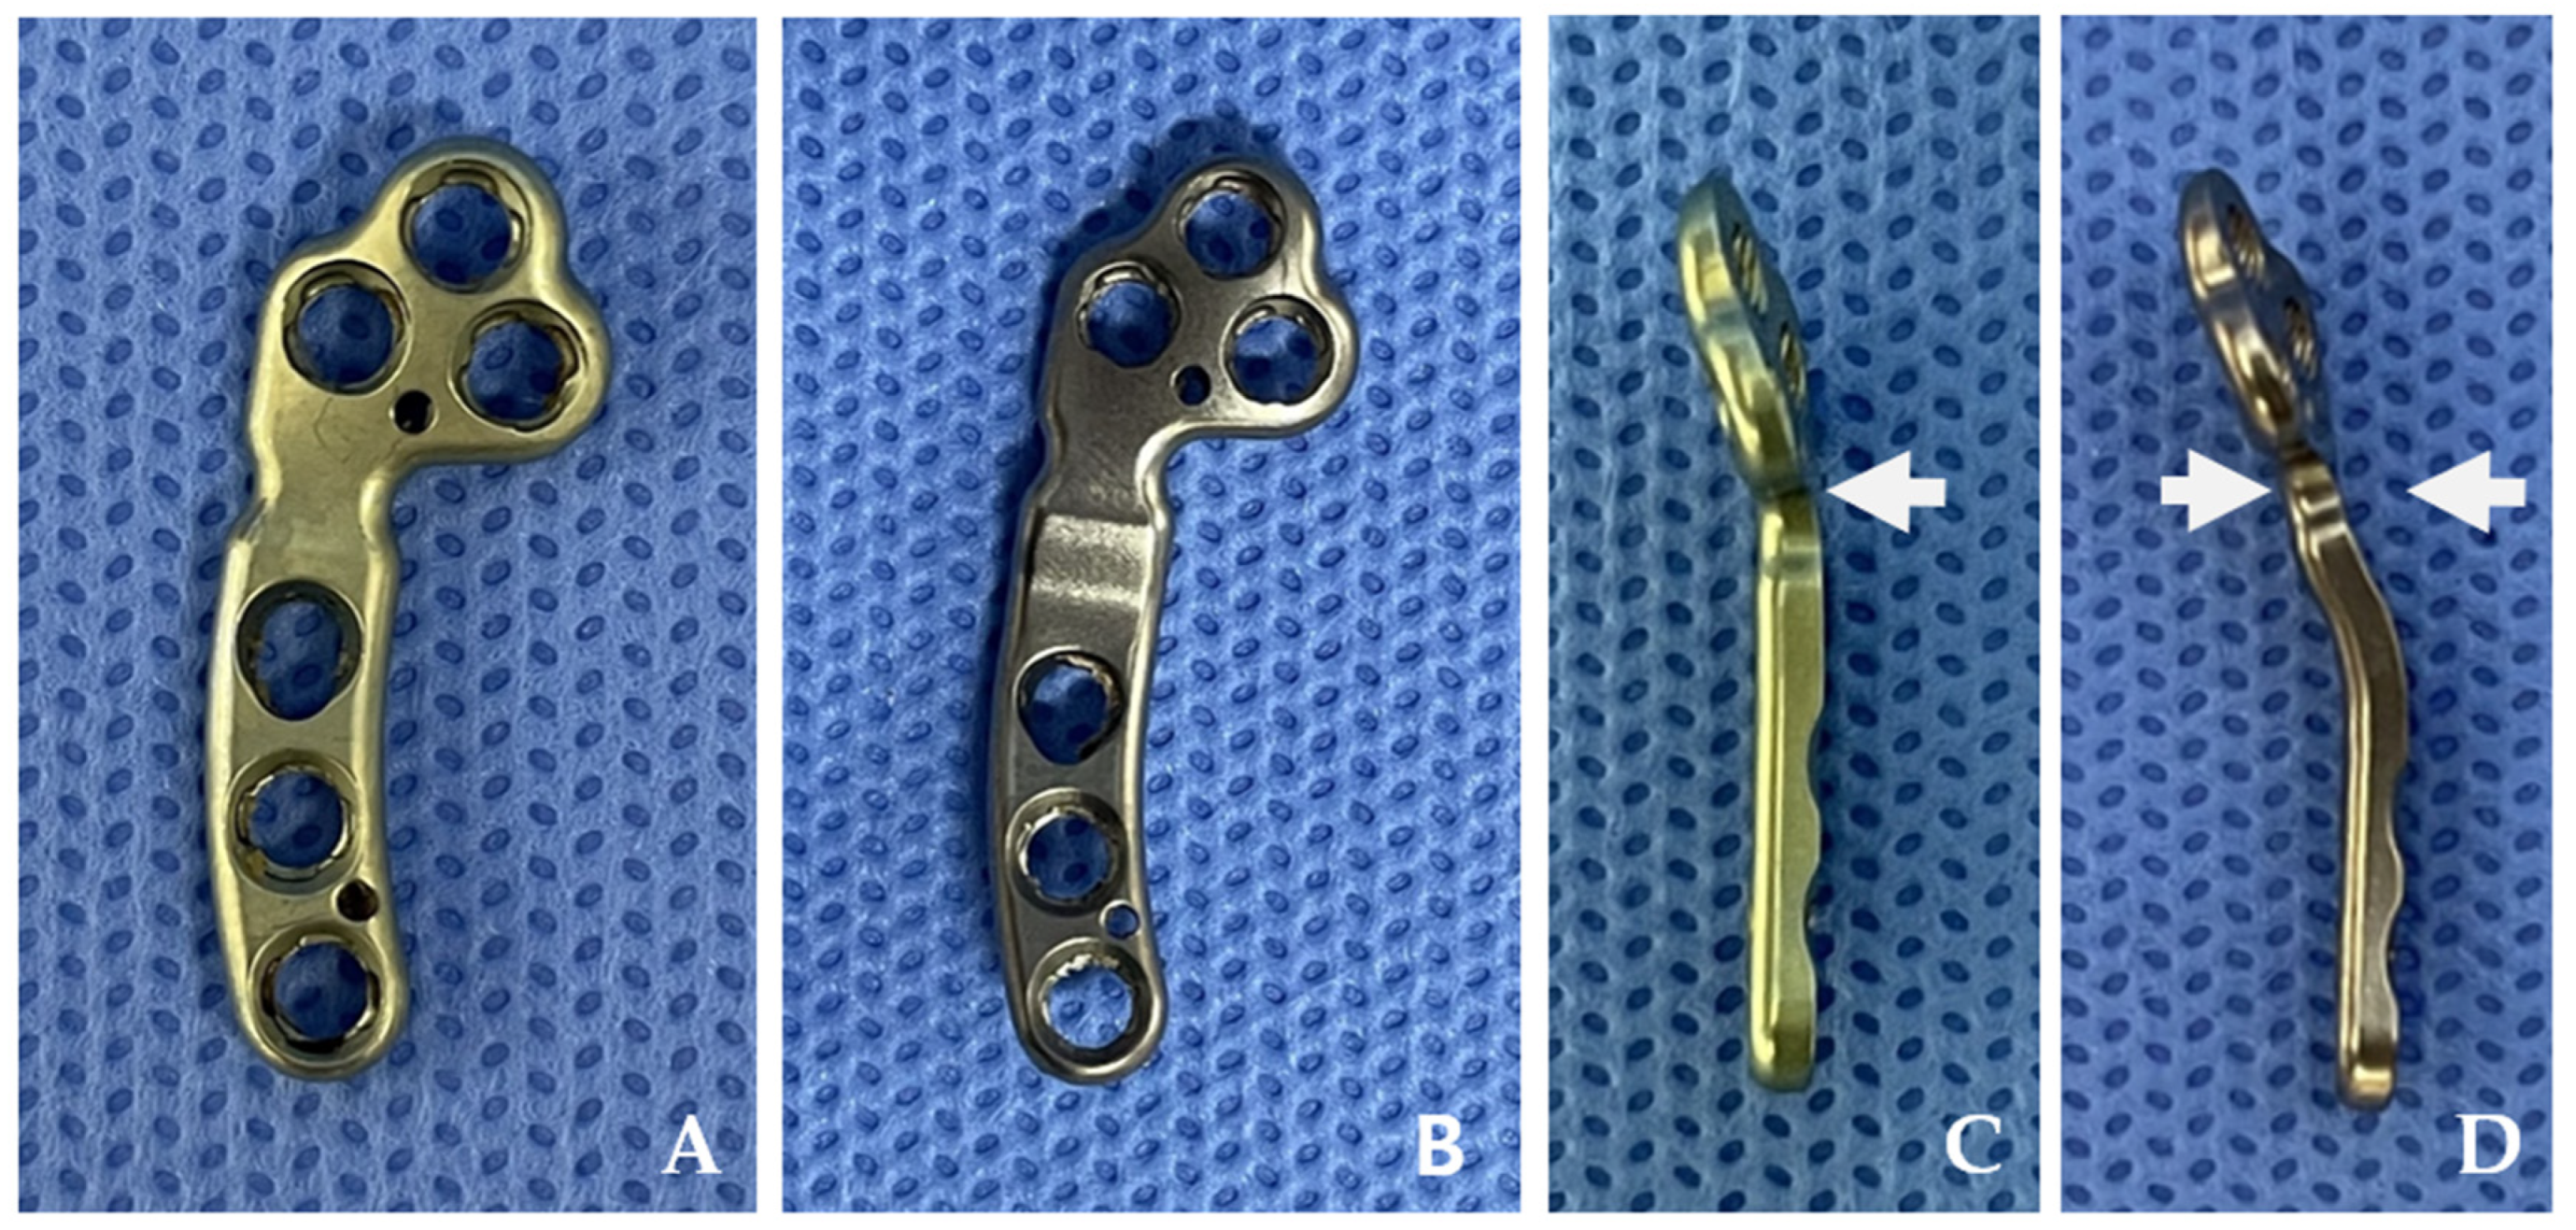

2.1. Plates